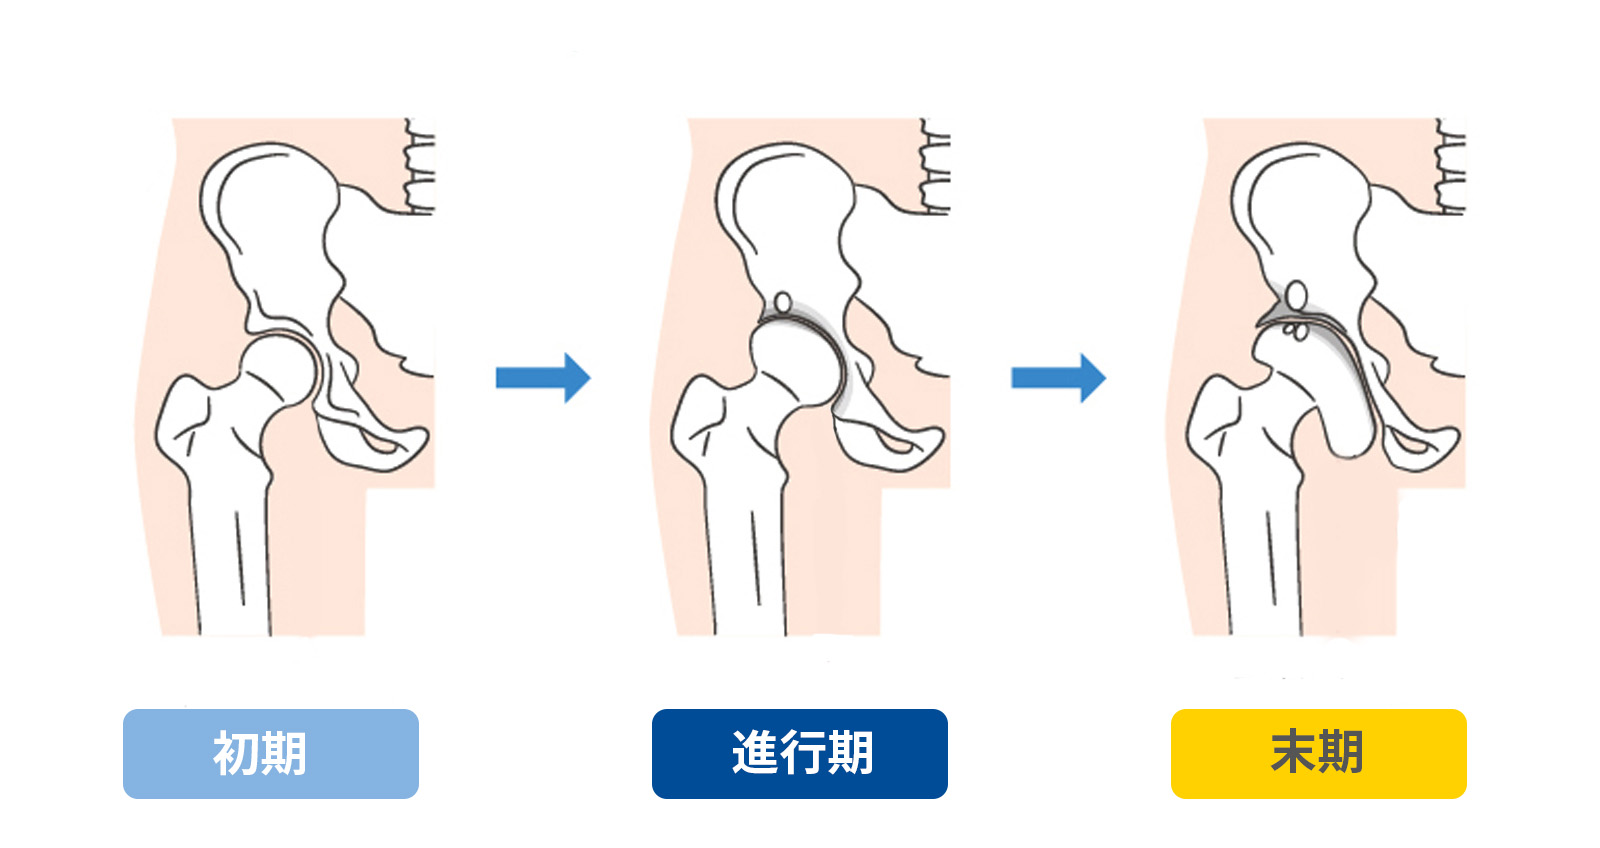

変形性股関節症

へんけいせいこかんせつしょう

加齢や臼蓋形成不全(※下で説明)などが主な原因で、股関節の軟骨がすり減り、骨同士がぶつかることで痛みや動かしにくさが生じます。中高年の女性に多く見られ、「歩く」「立ち上がる」「階段を上る」など、日常の動作が徐々につらくなっていきます。